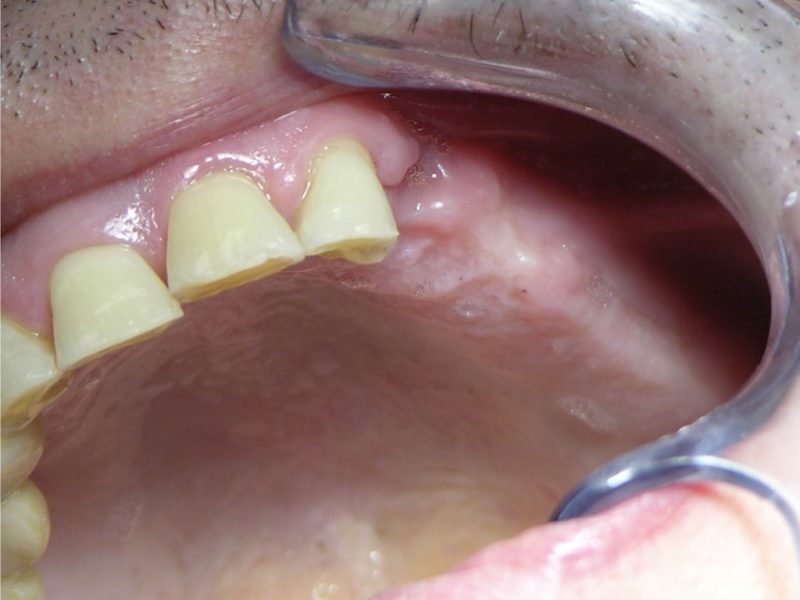

Patient's Data:

- Age: 58

- Sex: Male

- Smoker: Yes

- Pathologies: None

- Hygenic state: Bad

- Alergies: None

When the sinus Shneiderian membrane is very close to the implant site and does not allow the insertion of aregular sized implant the tretment can include the lift of the membrane. One of the complications we may find in this kind of practice is the migration of the implant inside the sinus. This occurs when during the surgical stages the membrane is torn and the implant is not enough stable in the bone and if it does not osteointegrate. To extract an implant from the sinus there is the need of a otorhinolaryngologist even if in some cases it can be done in the studio. To avoid such event we can apply a safety implant membrane. This thin titanium membrane can be fixed onto the implant right after the insertion and avoids the implant dislocation as it is adapted to the bone crest surrounding the implant site. To perform the surgery the line of compactors by B&B Dental has been used. These compactors carefully used thanks to their rounded head allow the gentle detachment and lift of the membrane to give room to bone regeneration materials. Their measurements correspond to implant diameter making it possible to insert an implant right after the sinus lifting procedure.